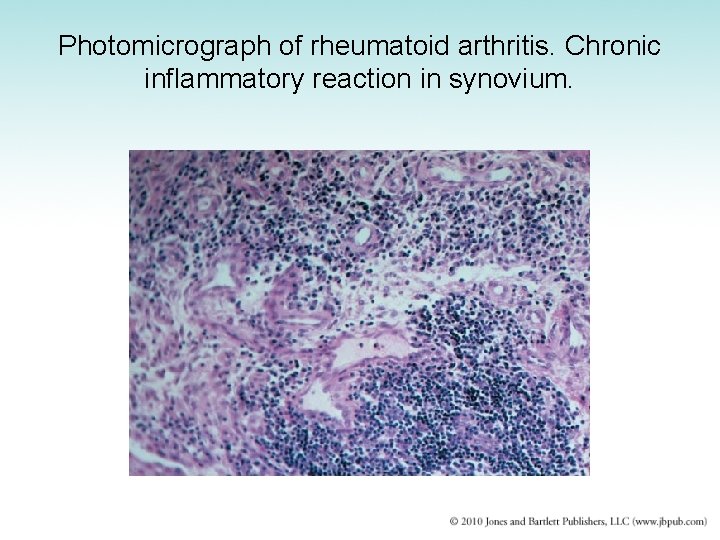

Photomicrograph of rheumatoid arthritis. Chronic inflammatory reaction in synovium.